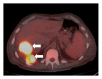

Primary pleural angiosarcomas are extremely rare. As of 2010, only around 50 case reports have been documented in the literature. Herein, we report the case of a 63-year-old gentleman who presented with a 3-month history of right-sided chest pain, dyspnea, and hemoptysis. Chest X-ray showed bilateral pleural effusion with partial bibasilar atelectasis. Ultrasound-guided thoracocentesis showed bloody and exudative pleural fluid. Cytologic examination was negative for malignant cells. An abdominal contrast-enhanced computed tomography (CT) scan showed two right diaphragmatic pleural masses. Whole-body positron emission tomography/computed tomography (PET/CT) scan showed two hypermetabolic fluorodeoxyglucose- (FDG-) avid lesions involving the right diaphragmatic pleura. CT-guided needle-core biopsy was performed and histopathological examination showed neoplastic cells growing mainly in sheets with focal areas suggestive of vascular spaces lined by cytologically malignant epithelioid cells. Immunohistochemical analysis showed strong positivity for vimentin, CD31, CD68, and Fli-1 markers. The overall pathological and immunohistochemical features supported the diagnosis of epithelioid angiosarcoma. The patient was scheduled for surgery in three weeks. Unfortunately, the patient died after one week after discharge secondary to pulseless ventricular tachycardia arrest followed by asystole. Moreover, we also present a brief literature review on pleural angiosarcoma.